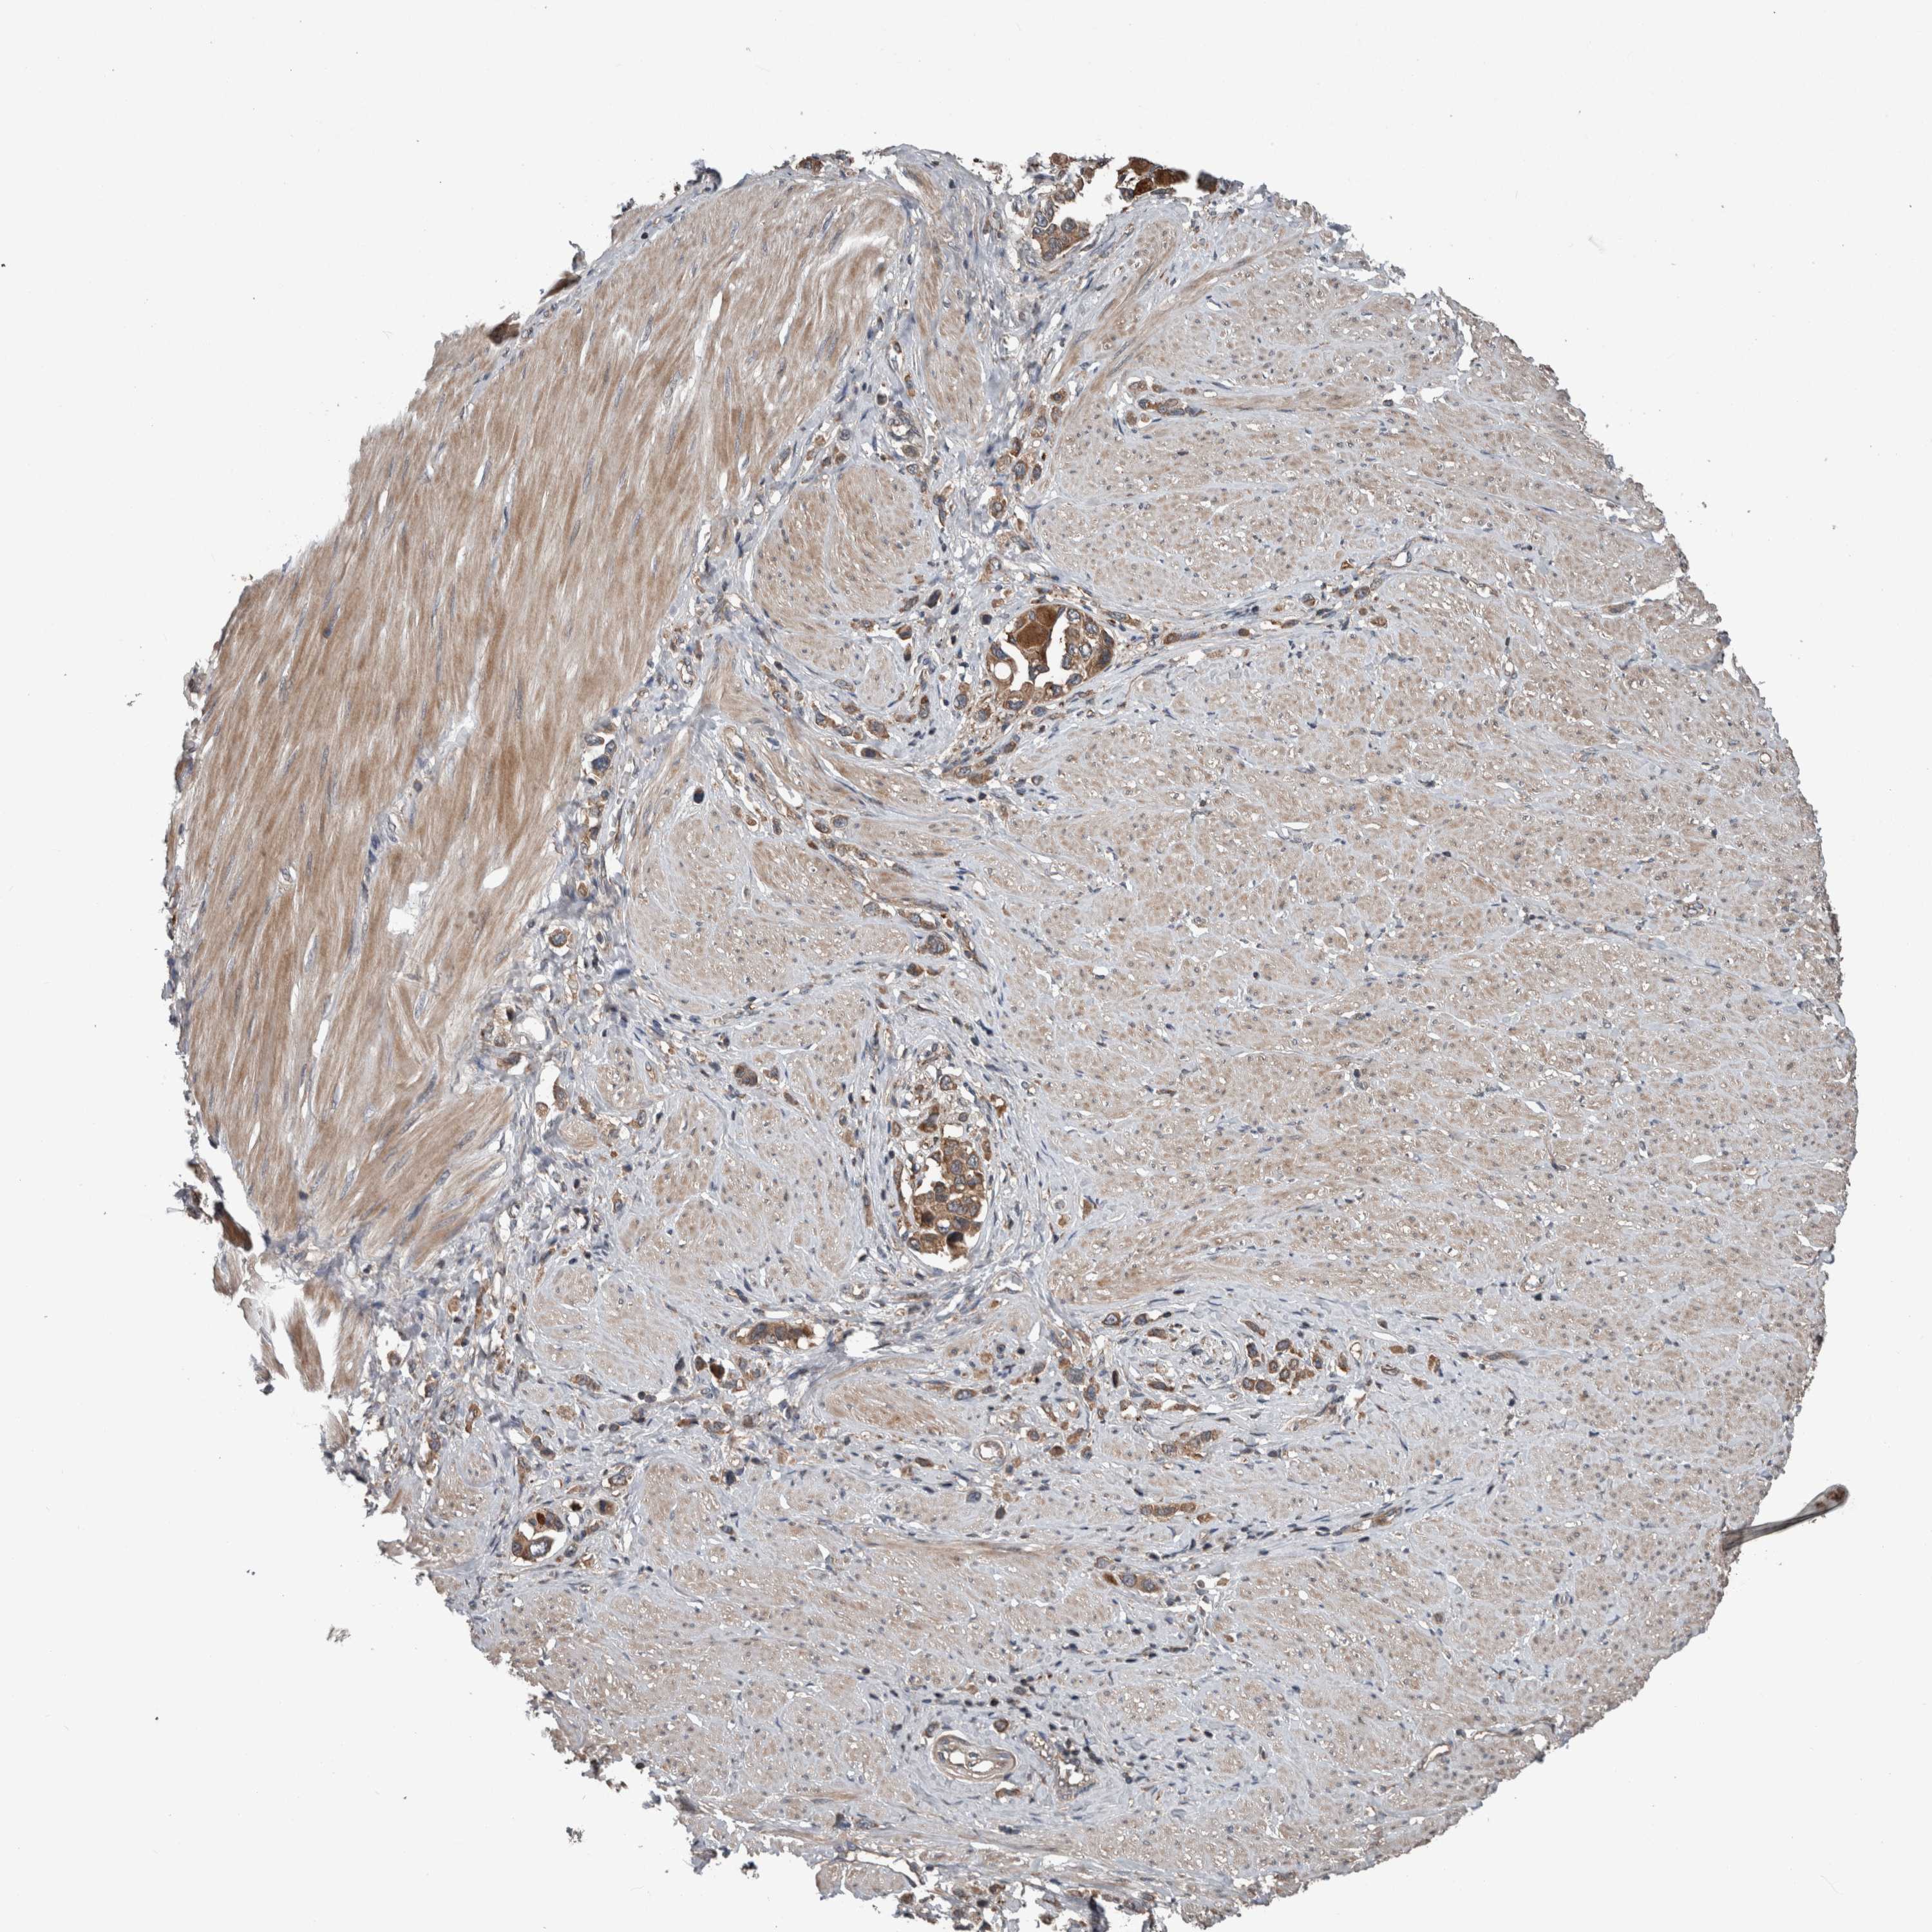

STOMACH CANCER - Protein expressioni

A mouse-over function shows sample information and annotation data. Click on an image to view it in a full screen mode. Samples can be filtered based on level of antibody staining by selecting one or several of the following categories: high, medium, low and not detected. The assay and annotation is described here.

Note that samples used for immunohistochemistry by the Human Protein Atlas do not correspond to samples in the TCGA dataset.

Antibody stainingi

Antibody staining in the annotated cell types in the current human tissue is reported as not detected, low, medium, or high, based on conventional immunohistochemistry profiling in selected tissues. This score is based on the combination of the staining intensity and fraction of stained cells.

Each image is clickable and will lead to virtual microscopy that enables deeper exploration of all samples and also displays staining intensity scores, fraction scores and subcellular localization as well as patient and tissue information for each sample.

Antibody HPA001620

Antibody HPA024184

Staining

High

Medium

Low

Not detected

Intensity

Strong

Moderate

Weak

Negative

Quantity

>75%

75%-25%

<25%

None

Location

Nuclear

Cytoplasmic/membranous

Cytoplasmic/membranous,nuclear

Adenocarcinoma, NOS